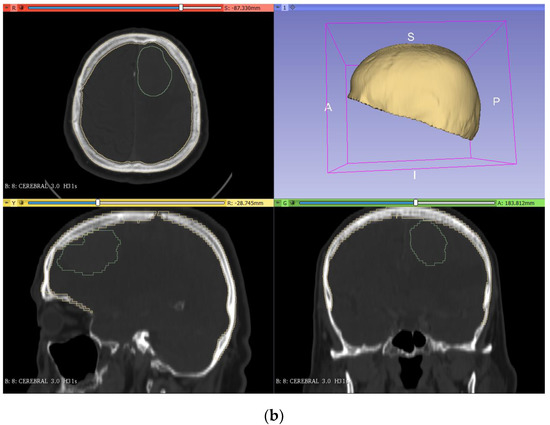

2.2.3. Brain Mold

In the making of the mold of the brain, the first step was to join the segmented model of the skull and the tumor (in the segment editor, ‘logical operators’ tool, ‘add’ operation) so that this mold had the shape of the tumor inside (Figure 4a). Then, the thickness was increased by 3 mm (‘margin’ tool) so that the molded brain had 3 mm of clearance with the skull. Finally, the model was cut (‘scissors’ tool) following the same plane as in the skull cutting (Figure 4b).

Figure 4.

Segmentation (a) and creation of the brain mold (b) from the DICOM images in 3DSlicer.